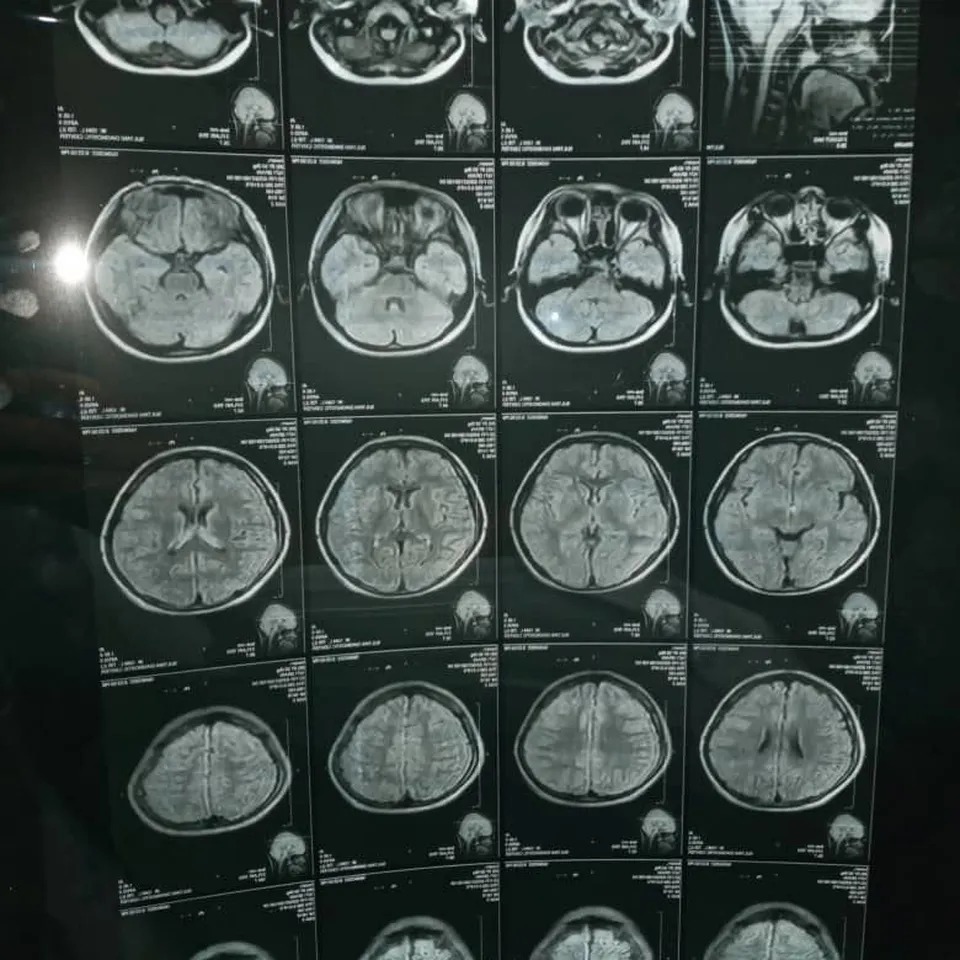

Hasan’s medical journey has been difficult and heartbreaking. Years ago, he was rushed to the hospital after experiencing a frightening episode characterized by tonic-clonic convulsions, sudden loss of consciousness, urinary incontinence, excessive oral secretions, and prolonged postictal drowsiness. These episodes were not isolated—his family recalls numerous incidents over the years where Hasan collapsed unexpectedly, injuring himself and terrifying those around him. Following a thorough evaluation, doctors diagnosed him with epilepsy, likely caused by a traumatic head injury he sustained earlier in life.

Since then, Hasan’s seizures have grown more frequent and debilitating. His condition now requires specialized neurological assessments and surgery to control the seizures and prevent further neurological damage. Unfortunately, such advanced medical care is not available in Afghanistan. His prognosis worsens with age, and doctors have advised that surgical intervention be pursued as soon as possible to offer the best outcome.